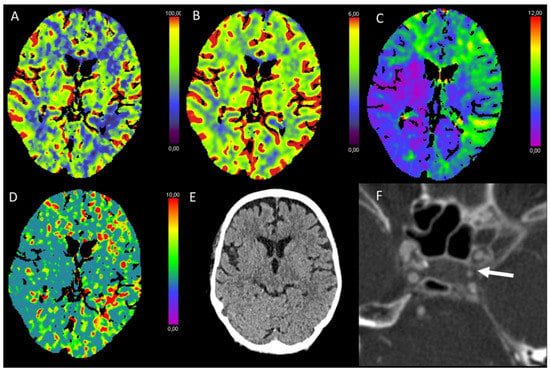

3.5. Hypotensive Cerebral Infarction (HCI) with Watershed Infarcts/Border Zones

3.6. Vasospasm